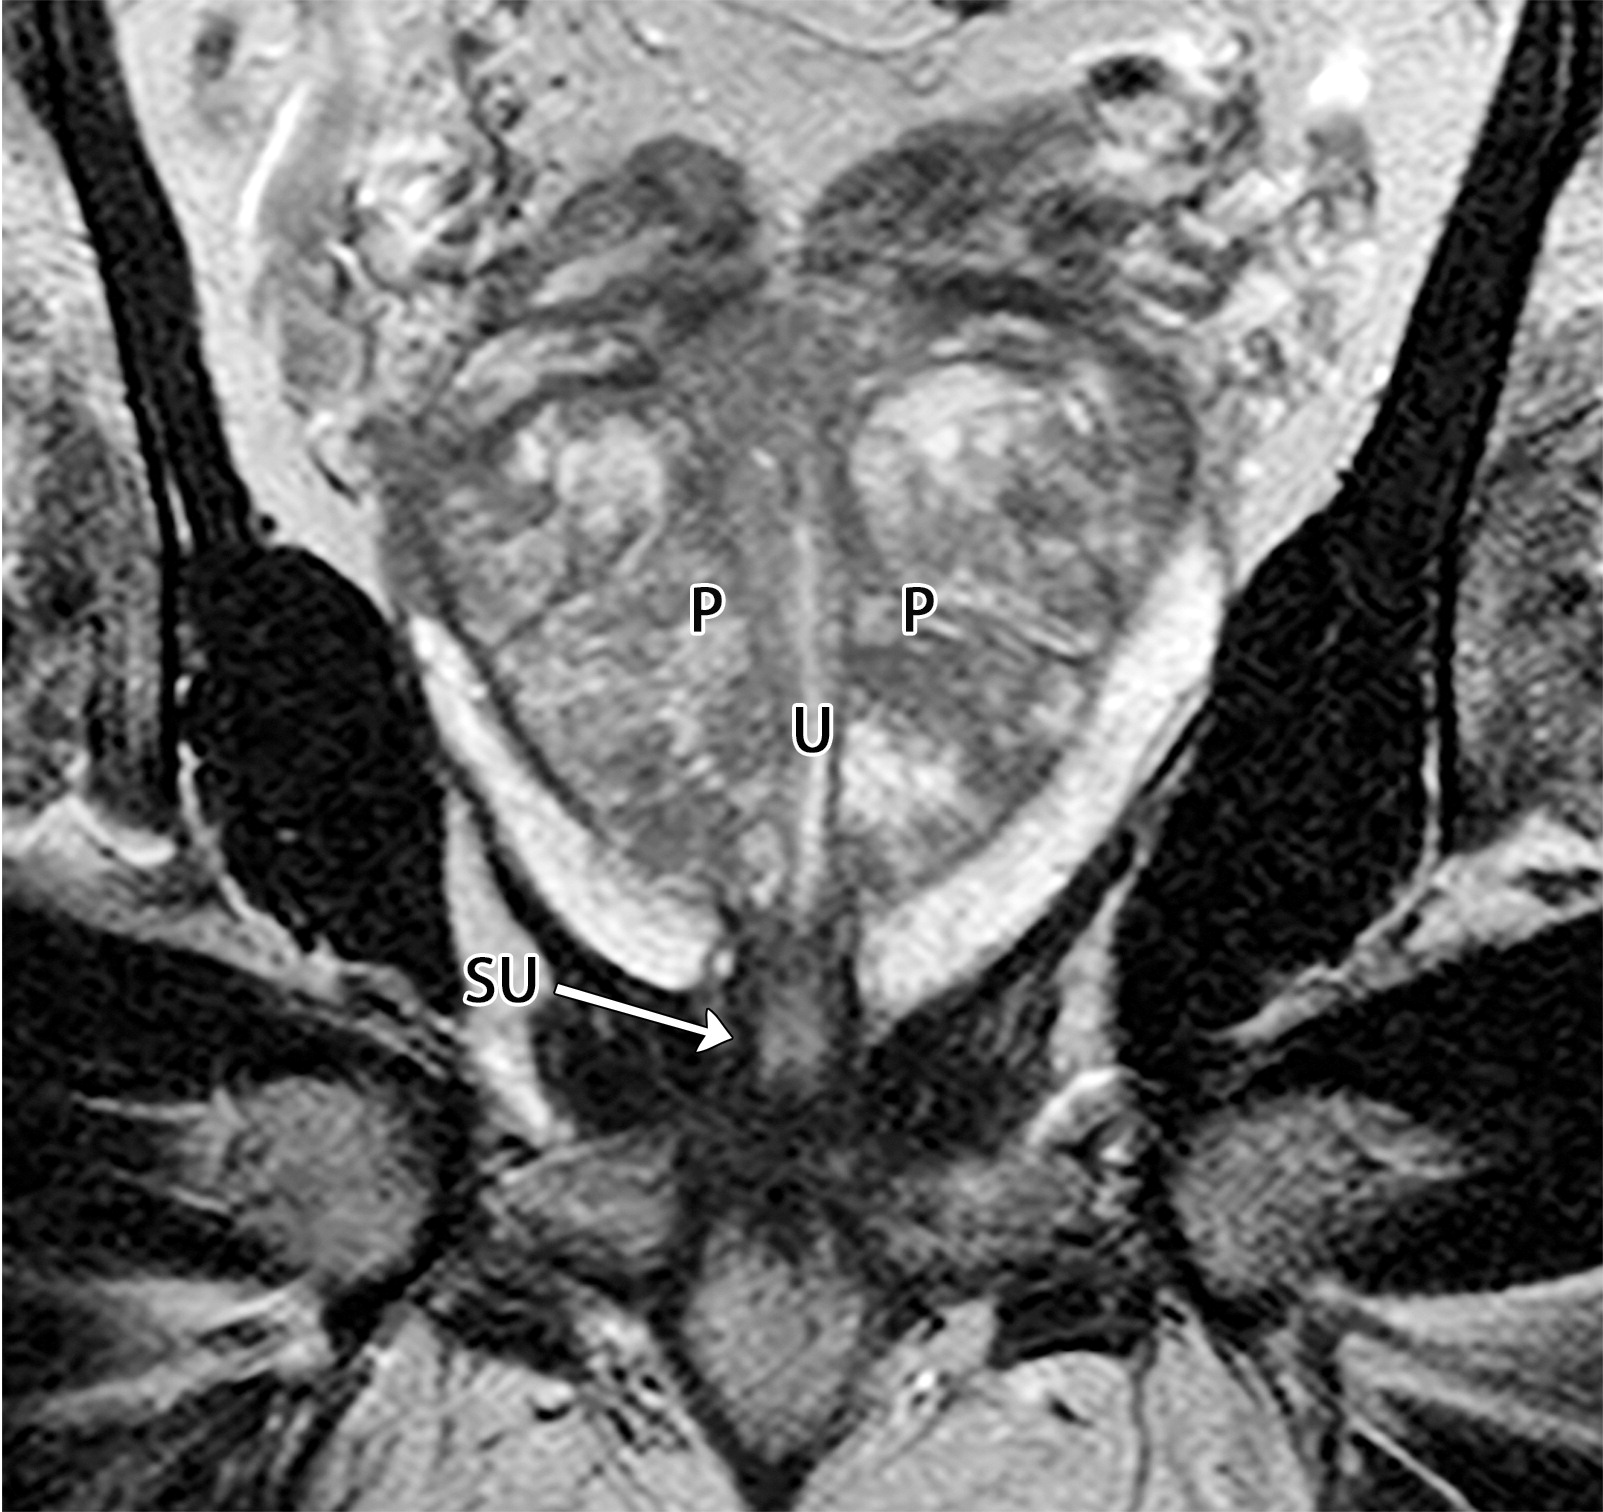

50岁以上男性骨盆和盆底的MRI解剖。

提肛肌(LA),由耻骨直肠肌(PR)、耻骨尾骨肌(PC)和髂尾骨肌(IC)组成;尾骨肌(C),前列腺(P),闭孔内肌(OI),会阴浅横肌(STP),球海绵体肌 (B), 坐骨海绵体肌(ISC),肛门外括约肌(EAS),肛门内括约肌(IAS),直肠(R),尿道括约肌(SU),也称为尿道外括约肌(U),它包围着整个膜性尿道。6774449af17bb1b8df6e83ab4e9fa158.jpeg